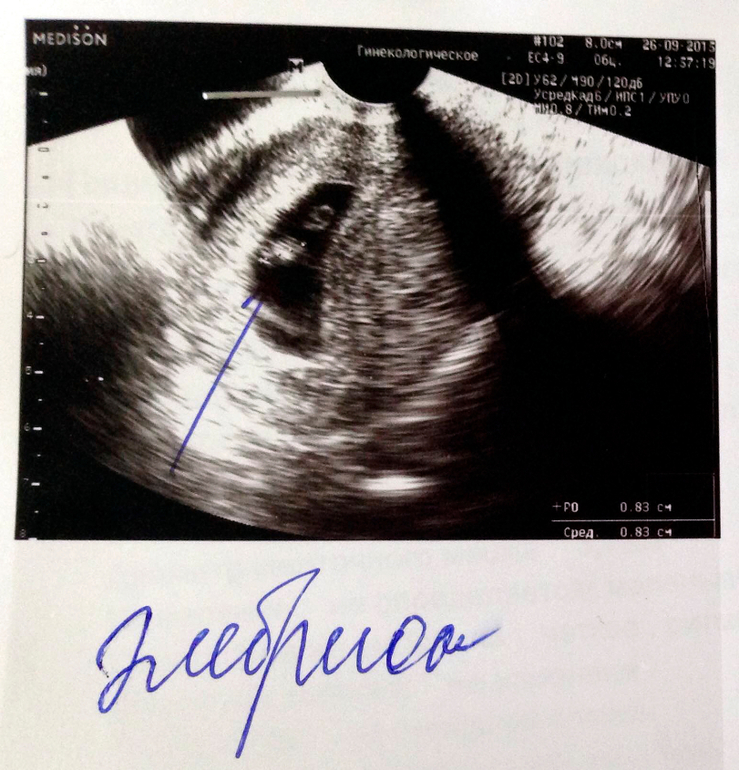

Вот и первые фото малыша :) Еще совсем маленький, 8,3 мм! Срок оказался еще меньше, чем я думала, всего 6 недель и 5-6 дней. Сердечко уже бьется, да так быстро - 137 ударов в минуту. Есть гипертонус передней стенки матки, назначили магний В6, буду успокаиваться. В следующий раз теперь только через месяц идти, 24 октября, будут делать скрининг на генетические патологии, а потом, если все хорошо, встану на учёт :)